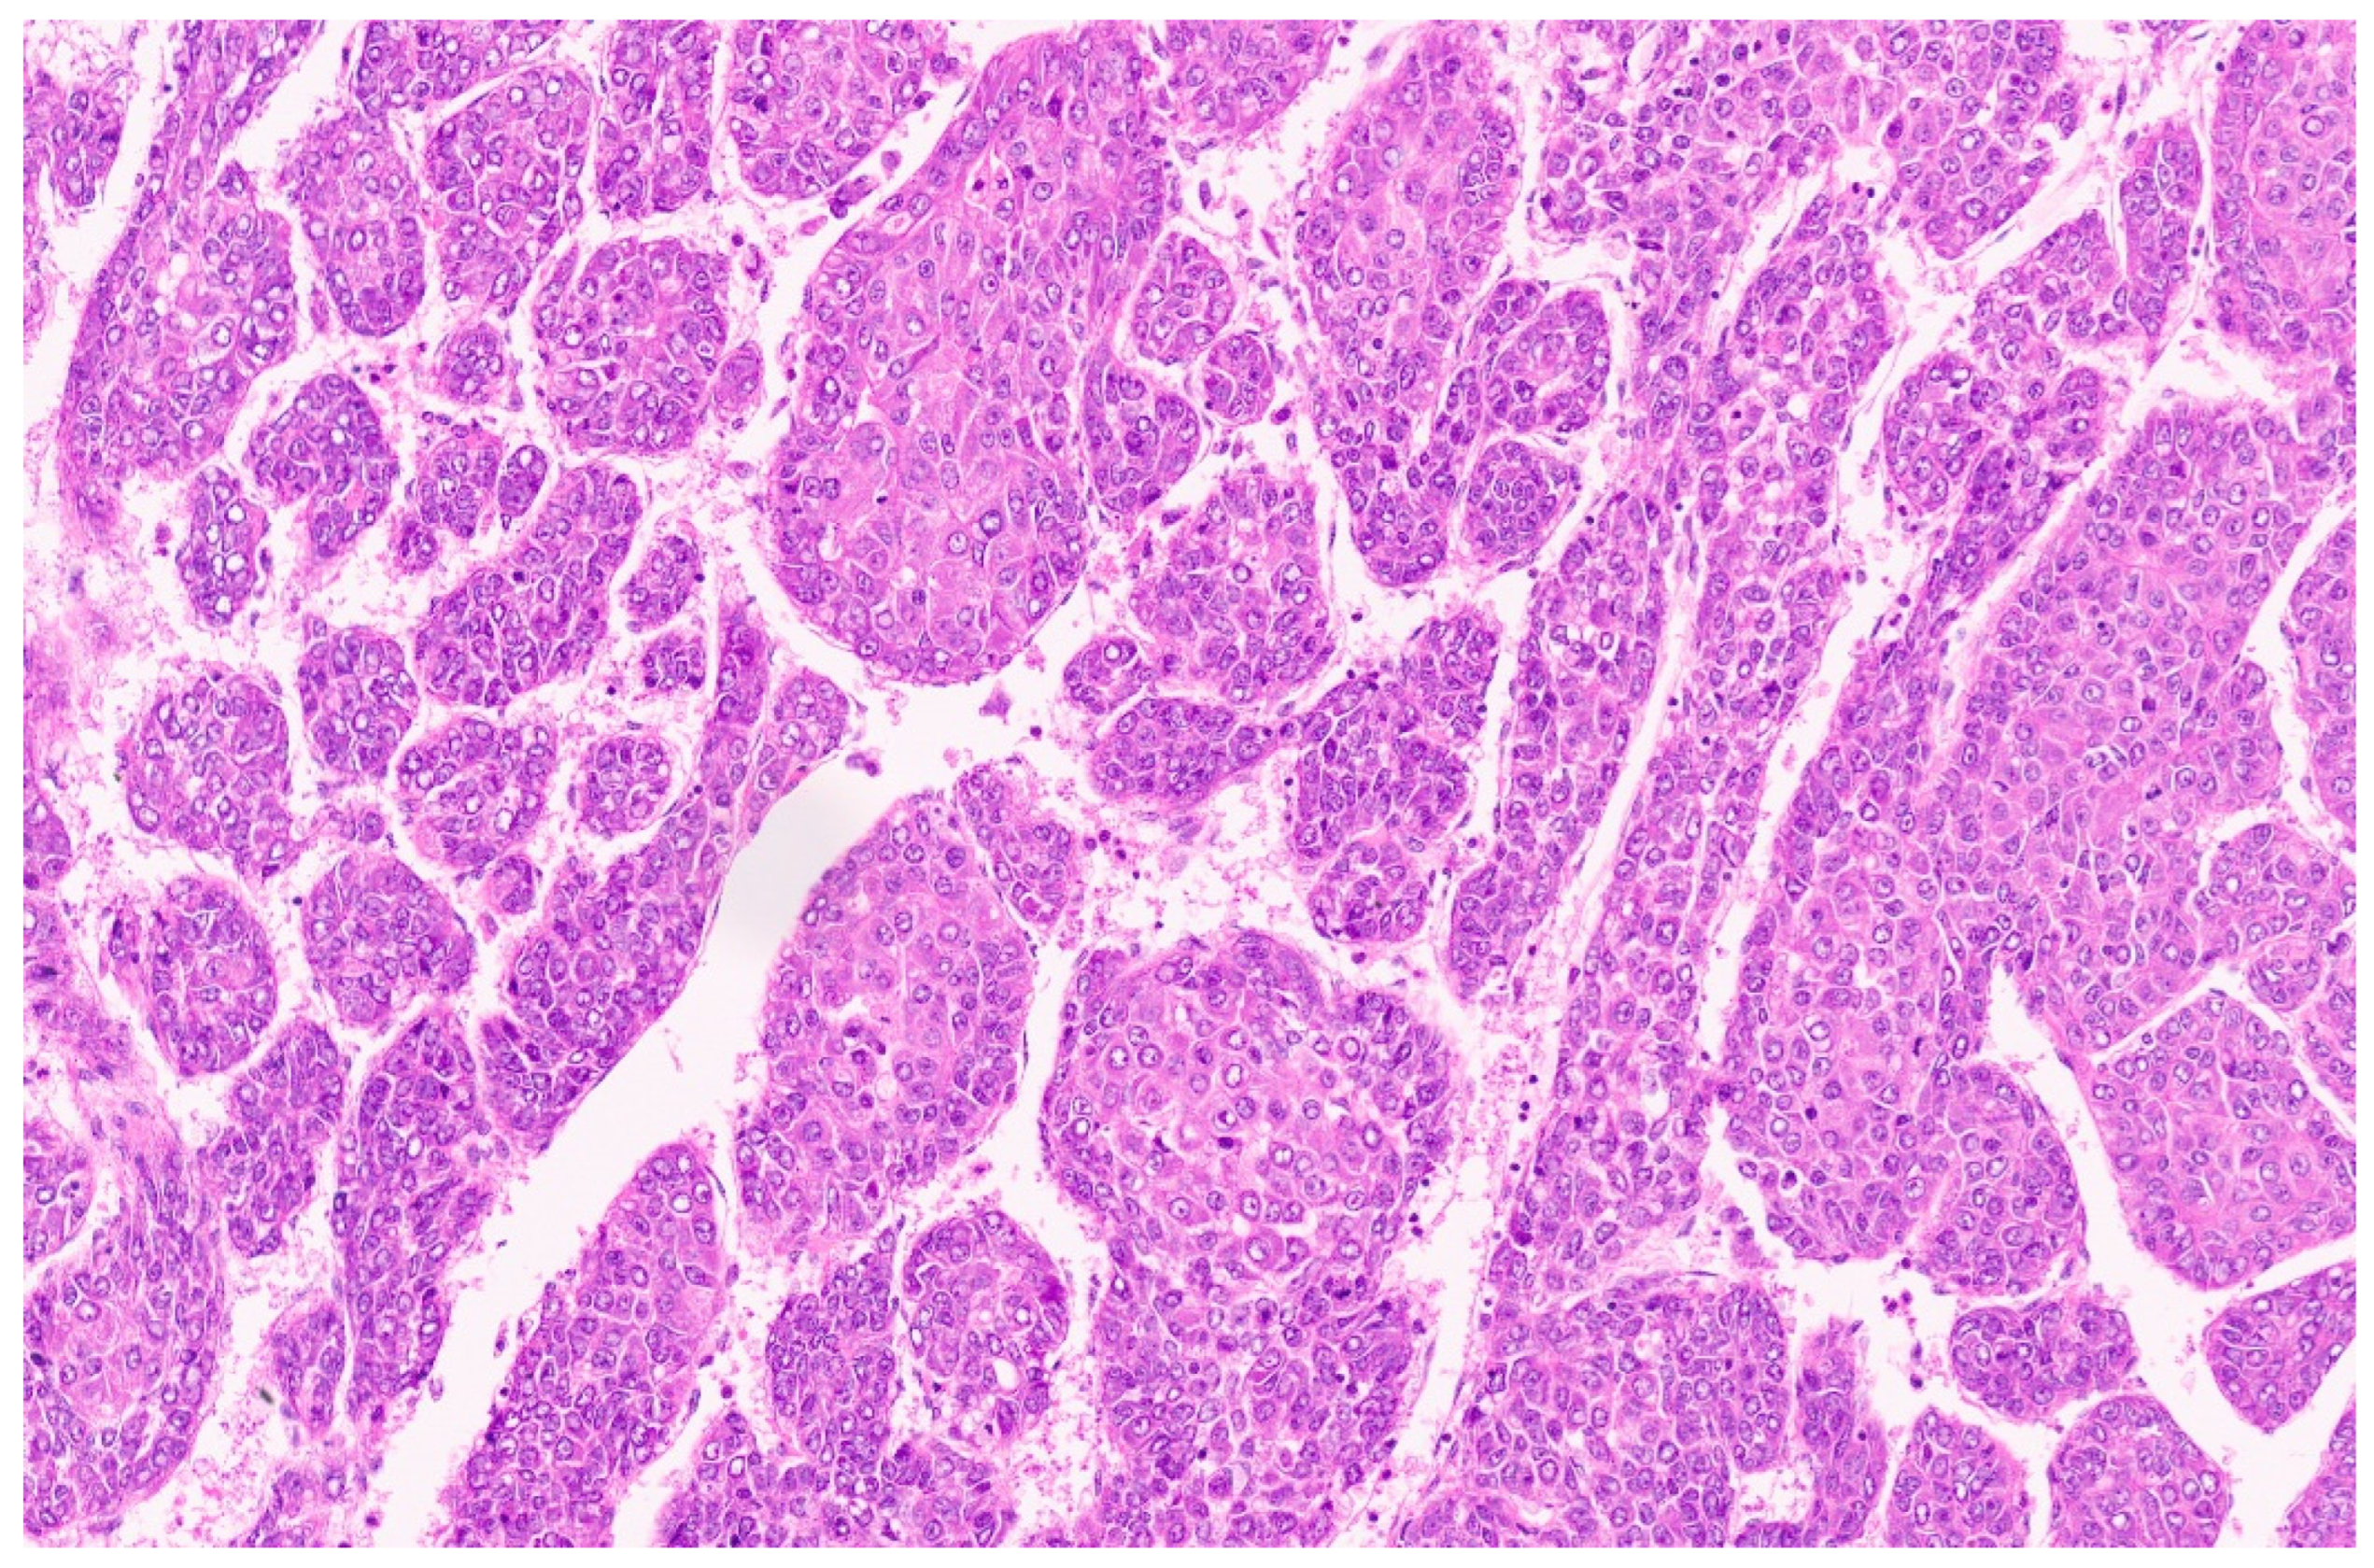

15.3. Pathology

| Classification | Architecture, Cell Size and Shape, Mitosis | Nucleus | Cytoplasm | IHC |

| Fetal | ||||

| 1–2-cell-thick cords of polygonal cells measuring 10–20 µ with central nuclei. Mitosis <2/10 HPF. Closely packed cells with high N/C ratio, well-delineated plasma membranes, mitosis ≥2/10HPF. | Round nucleus with finely stippled chromatin, well-delineated nuclear membrane, inconspicuous nucleoli. Round nuclei with fine chromatin. | Clear or finely granular and eosinophilic due to variable amounts of glycogen and lipids. Amphophilic cytoplasm due to decreased glycogen | Glypican 3 with finely granular cytoplasmic positivity, strong glutamine synthetase positivity, Hep par-1-positive, b-catenin membranous, cytoplasmic, with rare nuclear staining Strong coarse glypican 3 positivity, glutamine synthetase variable positivity, Hep par-1 positivity, uniform nuclear b-catenin positivity |